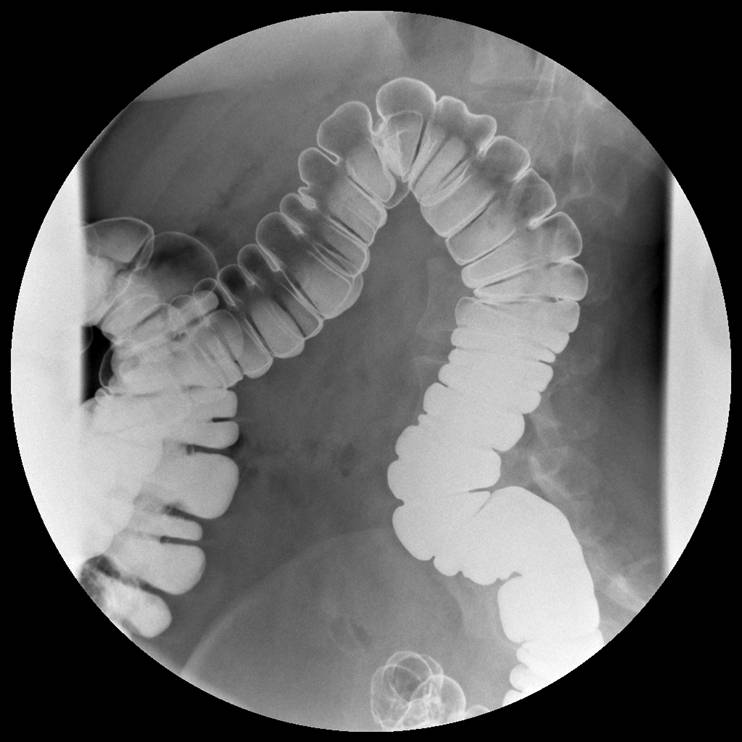

Tyktarm (venstre flexur), normal, røntgen

Kontrast og luft i den venstre øvre del af tarmen (venstre flexur).